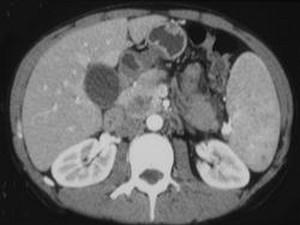

问题 女,56岁,腹部胀痛不适、食欲减退,影像表现如下图,最佳诊断是 ( )

选项 A、胰腺转移癌 B、胰腺假性囊肿 C、慢性胰腺炎 D、胰腺腺癌 E、急性胰腺炎

答案 D